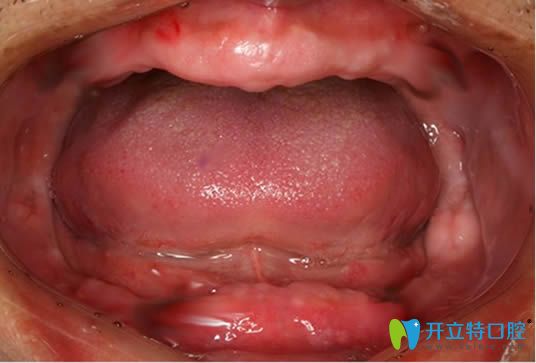

我今年65歲,早在10年前牙齒就掉的光光了,算起來我是整整帶了10年的活動假牙,真是后悔當初沒有做種植牙,而讓這個全口假牙害我一生啊....今天想在這里訴說下我悲催牙齒缺失經(jīng)歷吧。